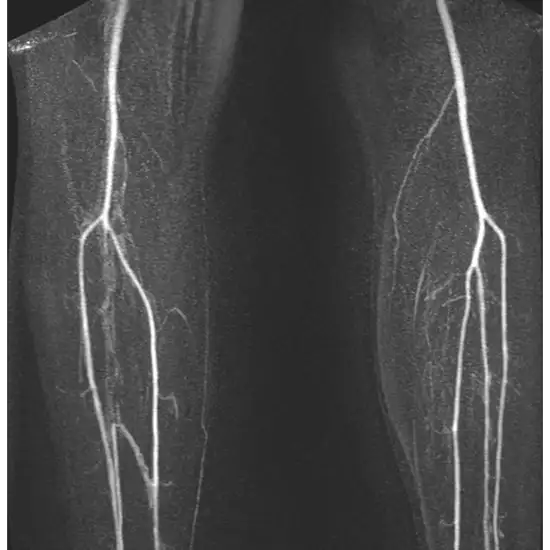

A left thigh MRI scan shows the thigh bone and surrounding cartilage, tendon, ligaments, muscles, and blood vessels.